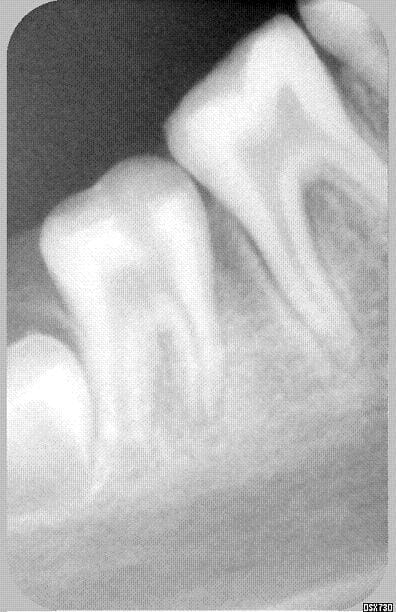

pour abonder dans ton sens concernant l'heredité, ci joint une photo du papa, cependant moins avancé que sa fille

pour diverger cependant, l'hérédité n'inclue pas forcément, dans ce cas les atteintes obligatoires des lactéales, elles étaient indemnes a l'époque

quand j'ai vu le papa, j'ai pensé qu'une simple mise a plat des puits dans certaines régions auraient peut etre permis de limiter le risque carieux, je n'ai pas osé...